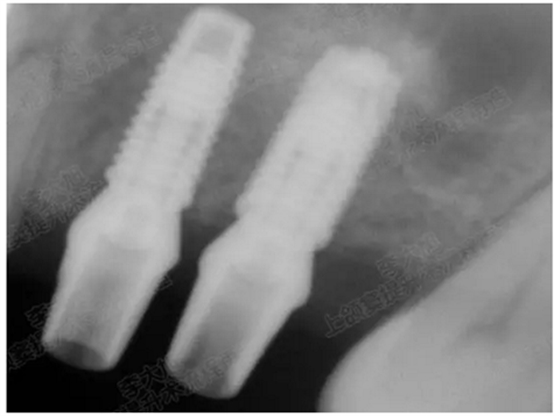

病例五

剩余不足1mm

112.png

提升10mm

113.png